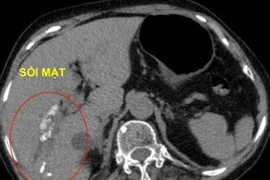

Không cần trải qua phẫu thuật, người bệnh có số lượng lớn sỏi đường mật trong và ngoài gan có thể được loại bỏ triệt để với can thiệp nội soi tán sỏi đường mật qua da.

Phương pháp xử lý tán sỏi đường mật qua da bằng laser được Trung tâm Tiêu hóa – Gan mật áp dụng là một đột phá với kỹ thuật xâm lấn tối thiểu, bảo tồn được túi mật nên bảo toàn được chức năng tiêu hóa và giúp quá trình hồi phục của bệnh nhân nhanh chóng.